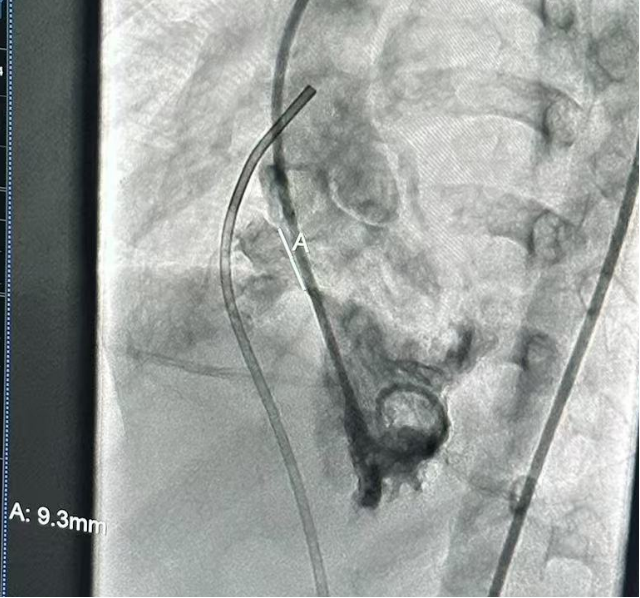

术中造影复测缺损大小

瘤体基底部约9.3mm |

本例为菜花型膜部瘤,造影可见室间隔右室面凸向右室腔的瘤样结构,头端呈分叶状,有多个出口与右室相通。根据术前超声和术中复测结果,瘤体基底部约10mm,主要的3股分流宽度为1.8mm、2mm和2.1mm。在此类多出口型膜部瘤室缺的封堵中,使用常规的金属封堵器可能受膨出瘤限制,盘面展开受限,封堵器可能无法完全覆盖所有破口,导致封堵不完全或出现残余分流,同时金属伞盘夹持力度过大还会引发心脏传导阻滞。然而全降解封堵器材料柔韧,既可保证封堵稳定,又不易压迫组织,植入后可自适应复杂的结构形态与组织运动,不易影响周围组织或瓣膜功能。因此经术者综合考虑后,最终选择了ABFDQ-II 10规格封堵器,搭配10F可降解封堵器介入输送系统进行封堵。术后超声下观察封堵器形态位置良好,无残余分流,封堵成功。